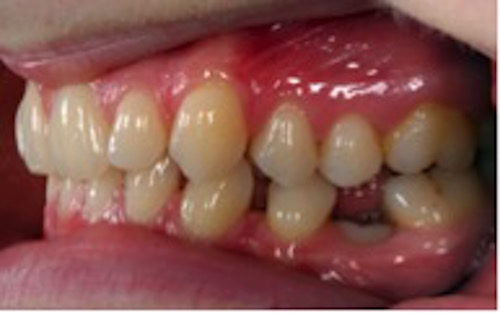

Infraocklusion av tänder innebär att tänderna befinner sig under ocklusalplanet hos angränsande tänder. Avståndet kan variera från någon millimeter till att ocklusalytan är under gingivakanten eller inte ens syns i munnen (1-4). I de flesta fall erupterar alla primära molarer upp till ocklusal kontakt med motstående tänder. Senare börjar en del hamna i infraocklusion och ibland blir de även ankylotiska.

I sällsynta fall kan primära molarer ses i infraocklusion redan i 3-4 årsåldern, men mest frekvent är infraocklusion i 9-10 års ålder (2). Omkring 14 % av barnen i dessa åldrar har en eller flera primära molarer i infraocklusion. Det förekommer dubbelt så ofta i underkäken som i överkäken. Infraocklusion av primära molarer förekommer ofta hos barn som även har andra tand- eller eruptionsavvikelser så som agenesi av premolarer, små eller tappformade överkäkslateraler, ektopisk eruption av överkäkens första permanenta molarer och retinerade överkäkshörntänder (5-8).